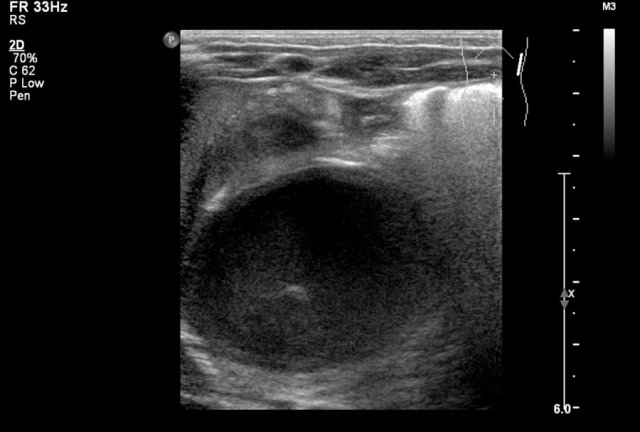

Here an ultrasound image of a five-month-old boy with an antenatally detected dilated pyelocalyceal system and no visible ureter, in accordance with a ureteropelvic junction stenosis.

On a sagittal image the dilated pyelocalyceal system is well seen.